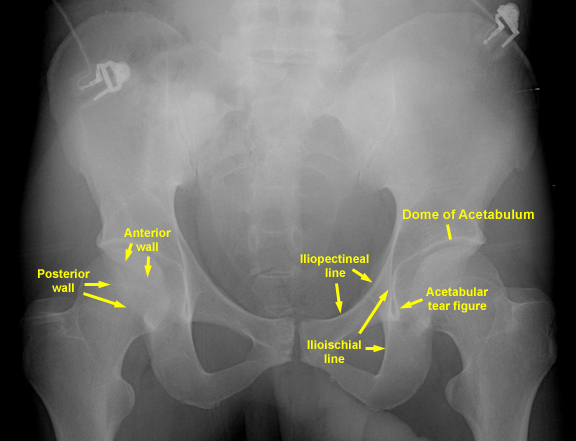

List specific things evaluated in an AP pelvis radiograph in the trauma setting.

Symphysis pubis <5 mm in width

Sacroiliac joint 2-4 mm in width

Pelvic ring should have no disruption

Obturator ring should have no disruption

Sacral foraminal arcs should be visible

Check TPs of lower lumbar vertebrae for fracture

Check the fat stripes: gluteal, iliopsoas, obturator

internus

Iliopectineal or arcuate line disruption # anterior column

Ilioischial line disruption # posterior column

Radiographic U or teardrop

Acetabular roof Sorcil

Anterior rim of the acetabulum

Posterior rim of the acetabulum

6 radiographic landmarks of the acetabulum: